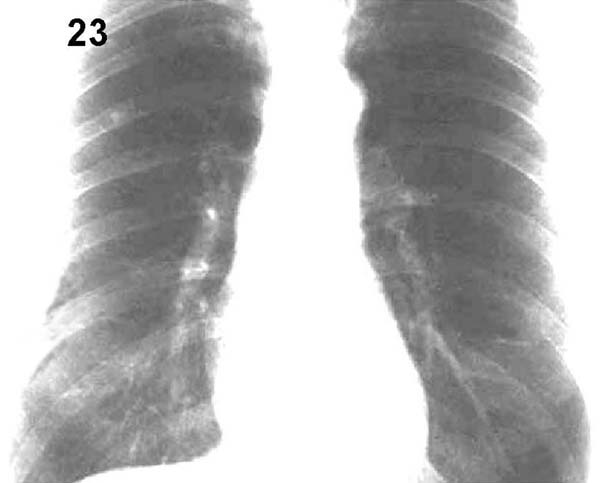

Placa 23